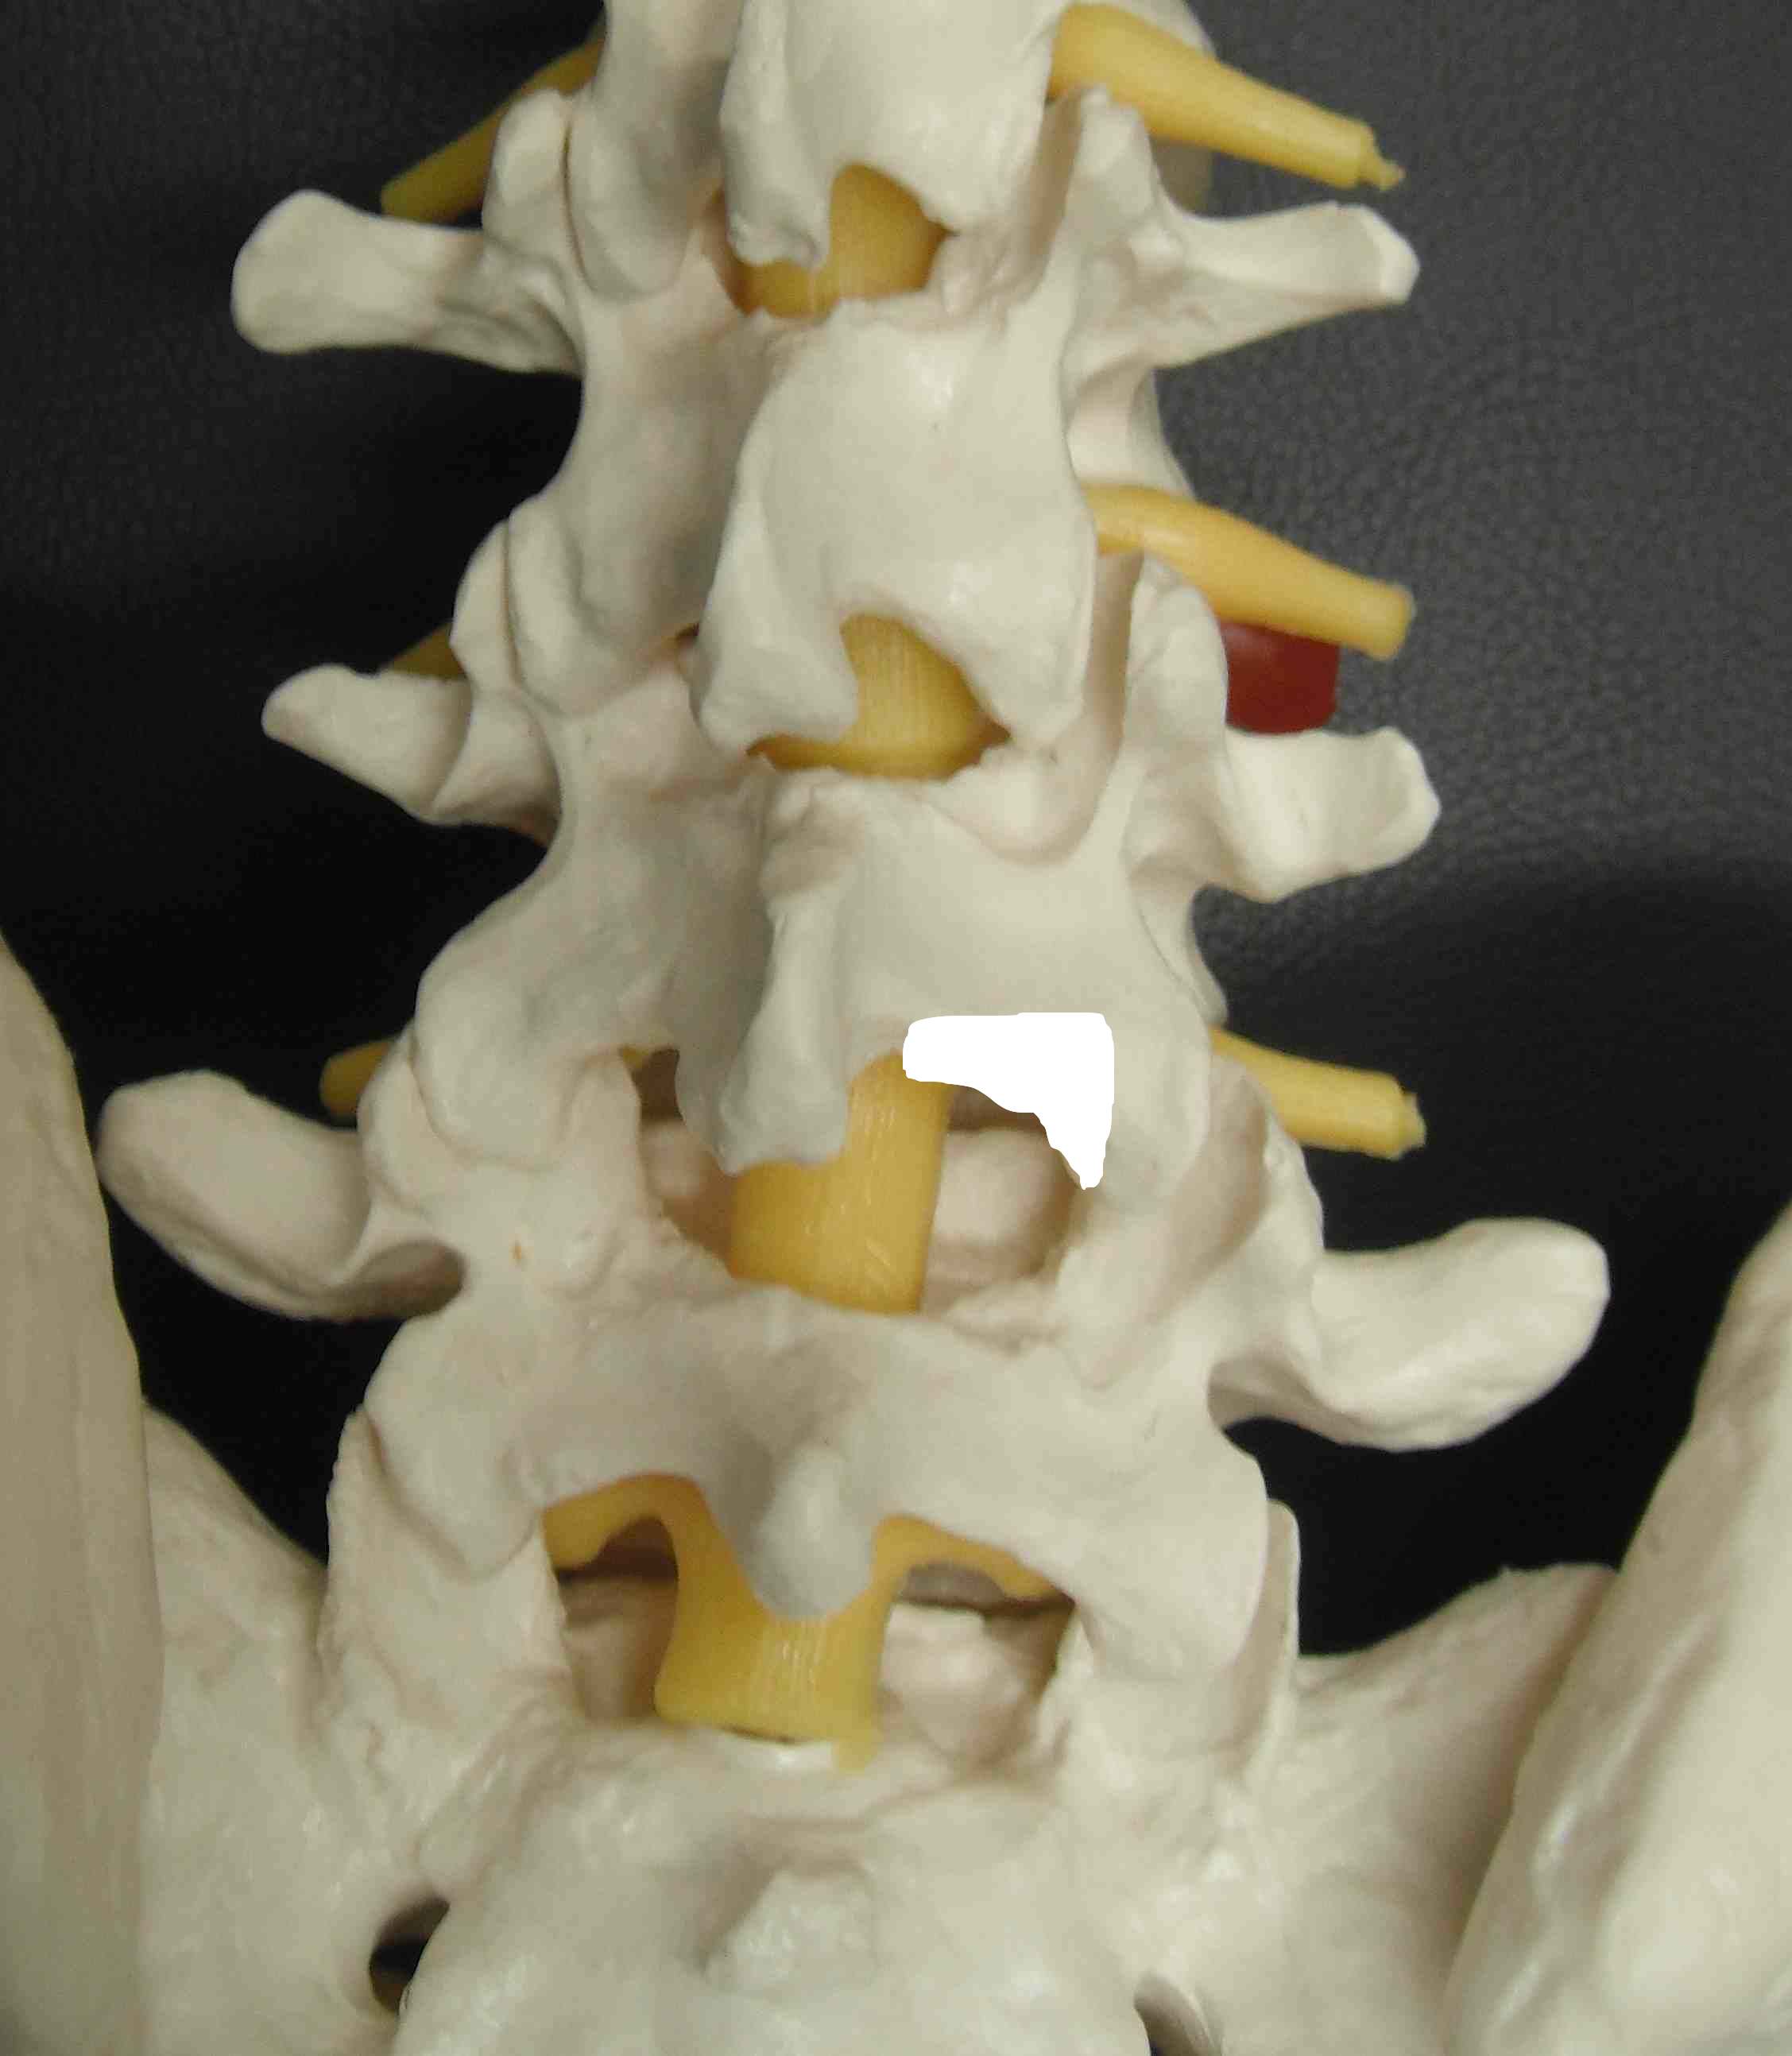

Deep Dissection

Expose Ligament Flavum

- attaches on top of inferior lamina to superior lamina

- find midline raphae

- incise flavum with scalpel over inferior laminae

- create flap of flavum

- use Watson Cheyne Dissector to gently dissect off dural adhesions

- remove flavum laterally

- 1, 2 or 3 mm 40° Kerrison Rongeur

- see fat overlying blue dura

Remove inferior aspect of superior lamina

- will take up to L4/5 disc

- resect medial two thirds of superior facet / lower one third inferior facet